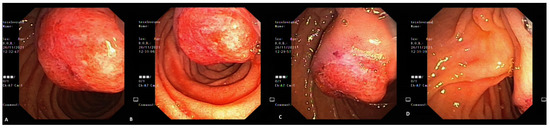

2. Case Report 1

3. Case Report 2

4. Case Report 3